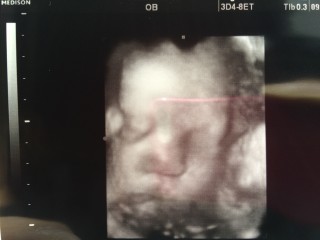

32w2d1705gの男の子です! 今日はとても綺麗に撮れたと先生にも看護師さんにも誉めて頂きました(´∀`) 丸い鼻は私似かな?笑 早く会いたいよー※。.:*:・'°☆